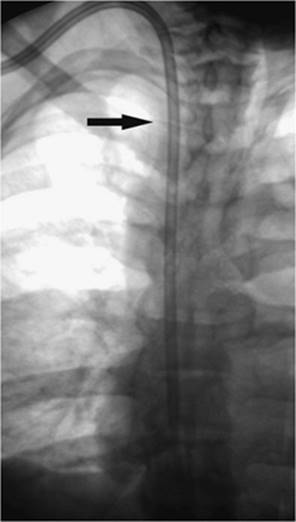

000415

Figure 35.7. A 70-year-old female with progressive pneumothorax following placement of transvenous cardiac pacing device. A: Arrows indicate the partially collapsed left lung following pacing device placement. B: Fluoroscopic image obtained at time of 8 Fr chest tube insertion. The tube was placed slightly lower than the usual apical position to avoid potential damage to the pacing device or wires. C: Following chest tube insertion, the pneumothorax was evacuated with syringe aspiration of the air. Follow-up chest radiograph demonstrates near-completed resolution. The chest tube was connected to Pleur-Evac drainage system.